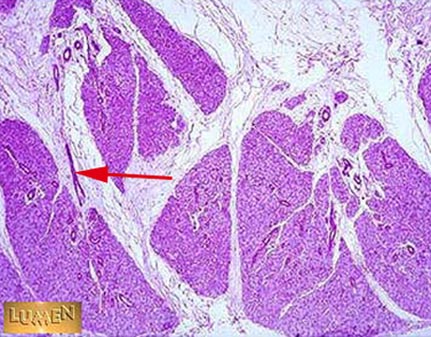

What structure is indicated by the arrow?

Interlobular duct